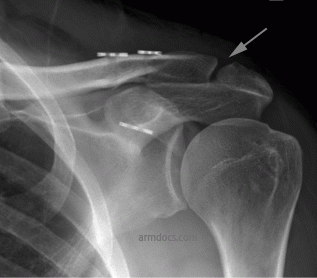

This protocol is applicable to patients treated surgically for acromioclavicular joint separations.